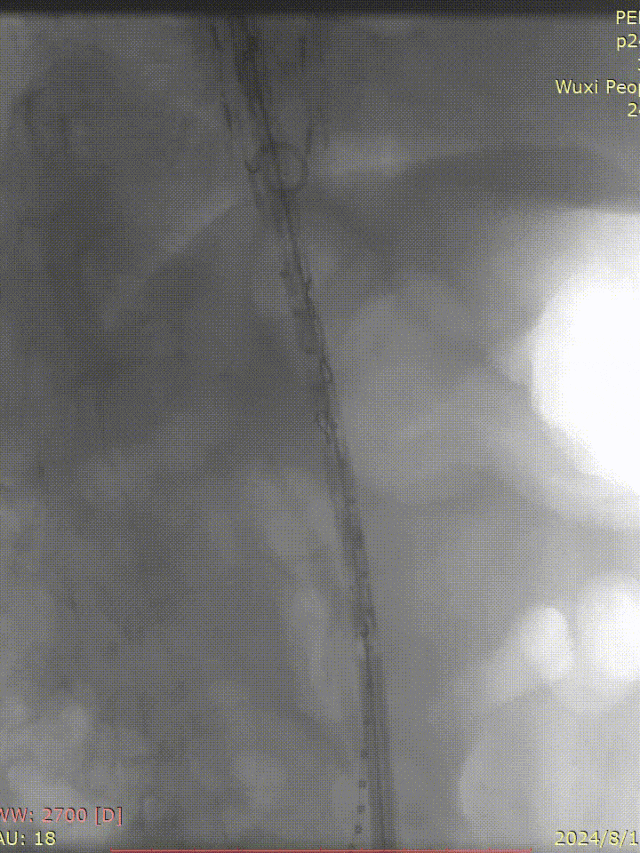

病史:54岁男性,发现胸腹主动脉夹层动脉瘤四天,2011年曾行A型夹层手术史,术后10年未复查。

手术方案:全麻下行胸腹主动脉夹层覆膜支架腔内隔绝,CA、SMA、双侧肾动脉体外开窗重建术。

I期腔内修复过程:

肾动脉至肠上区无破口,病情进展后又进行了二期干预

胸腹主动脉瘤四开窗内脏区重建+远端髂总大破口栓塞

术后效果良好,各分支通畅